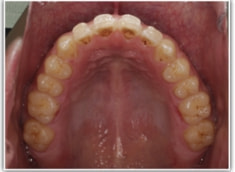

開咬(かいこう:オープンバイト)ケース

治療法:表の矯正(T21ブラケット)

(インプラントアンカーや外科矯正は行わず、エラスティックと機能訓練のみ)

治療前